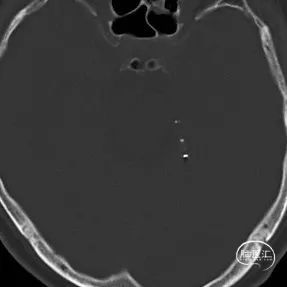

术后CT提示支架打开良好。

术前CT